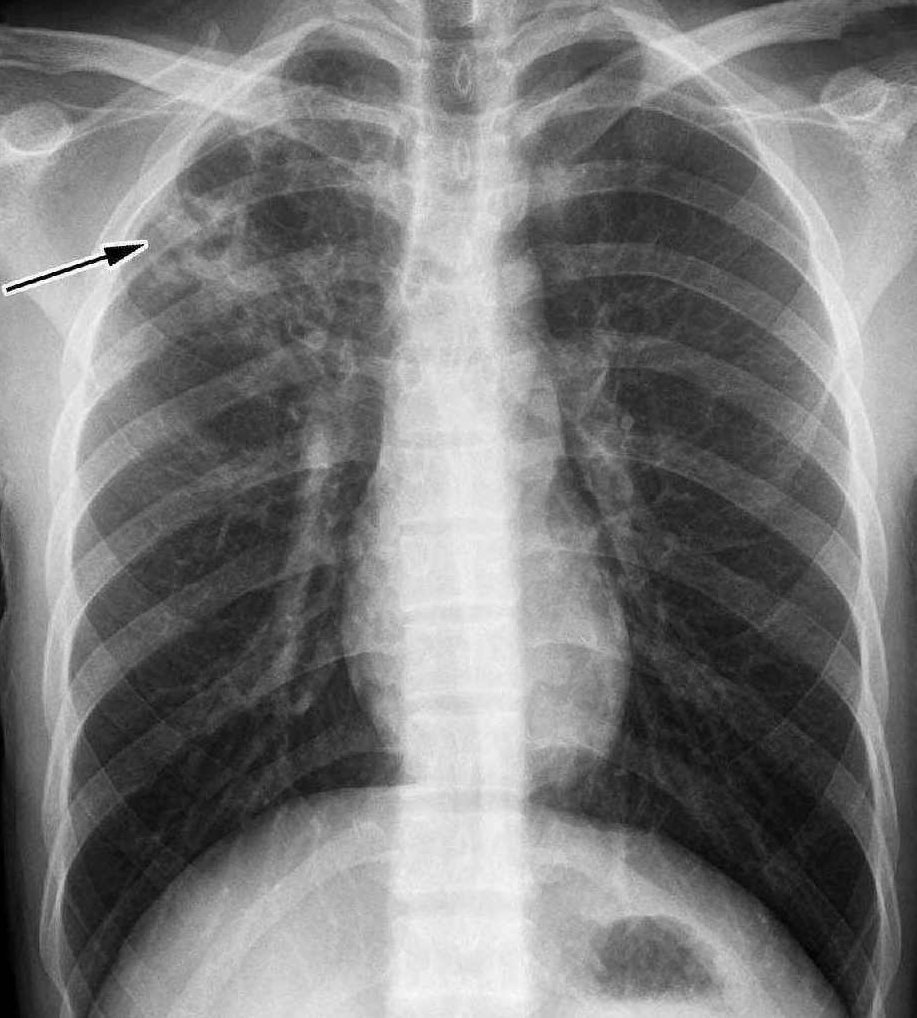

高微微 肺结核